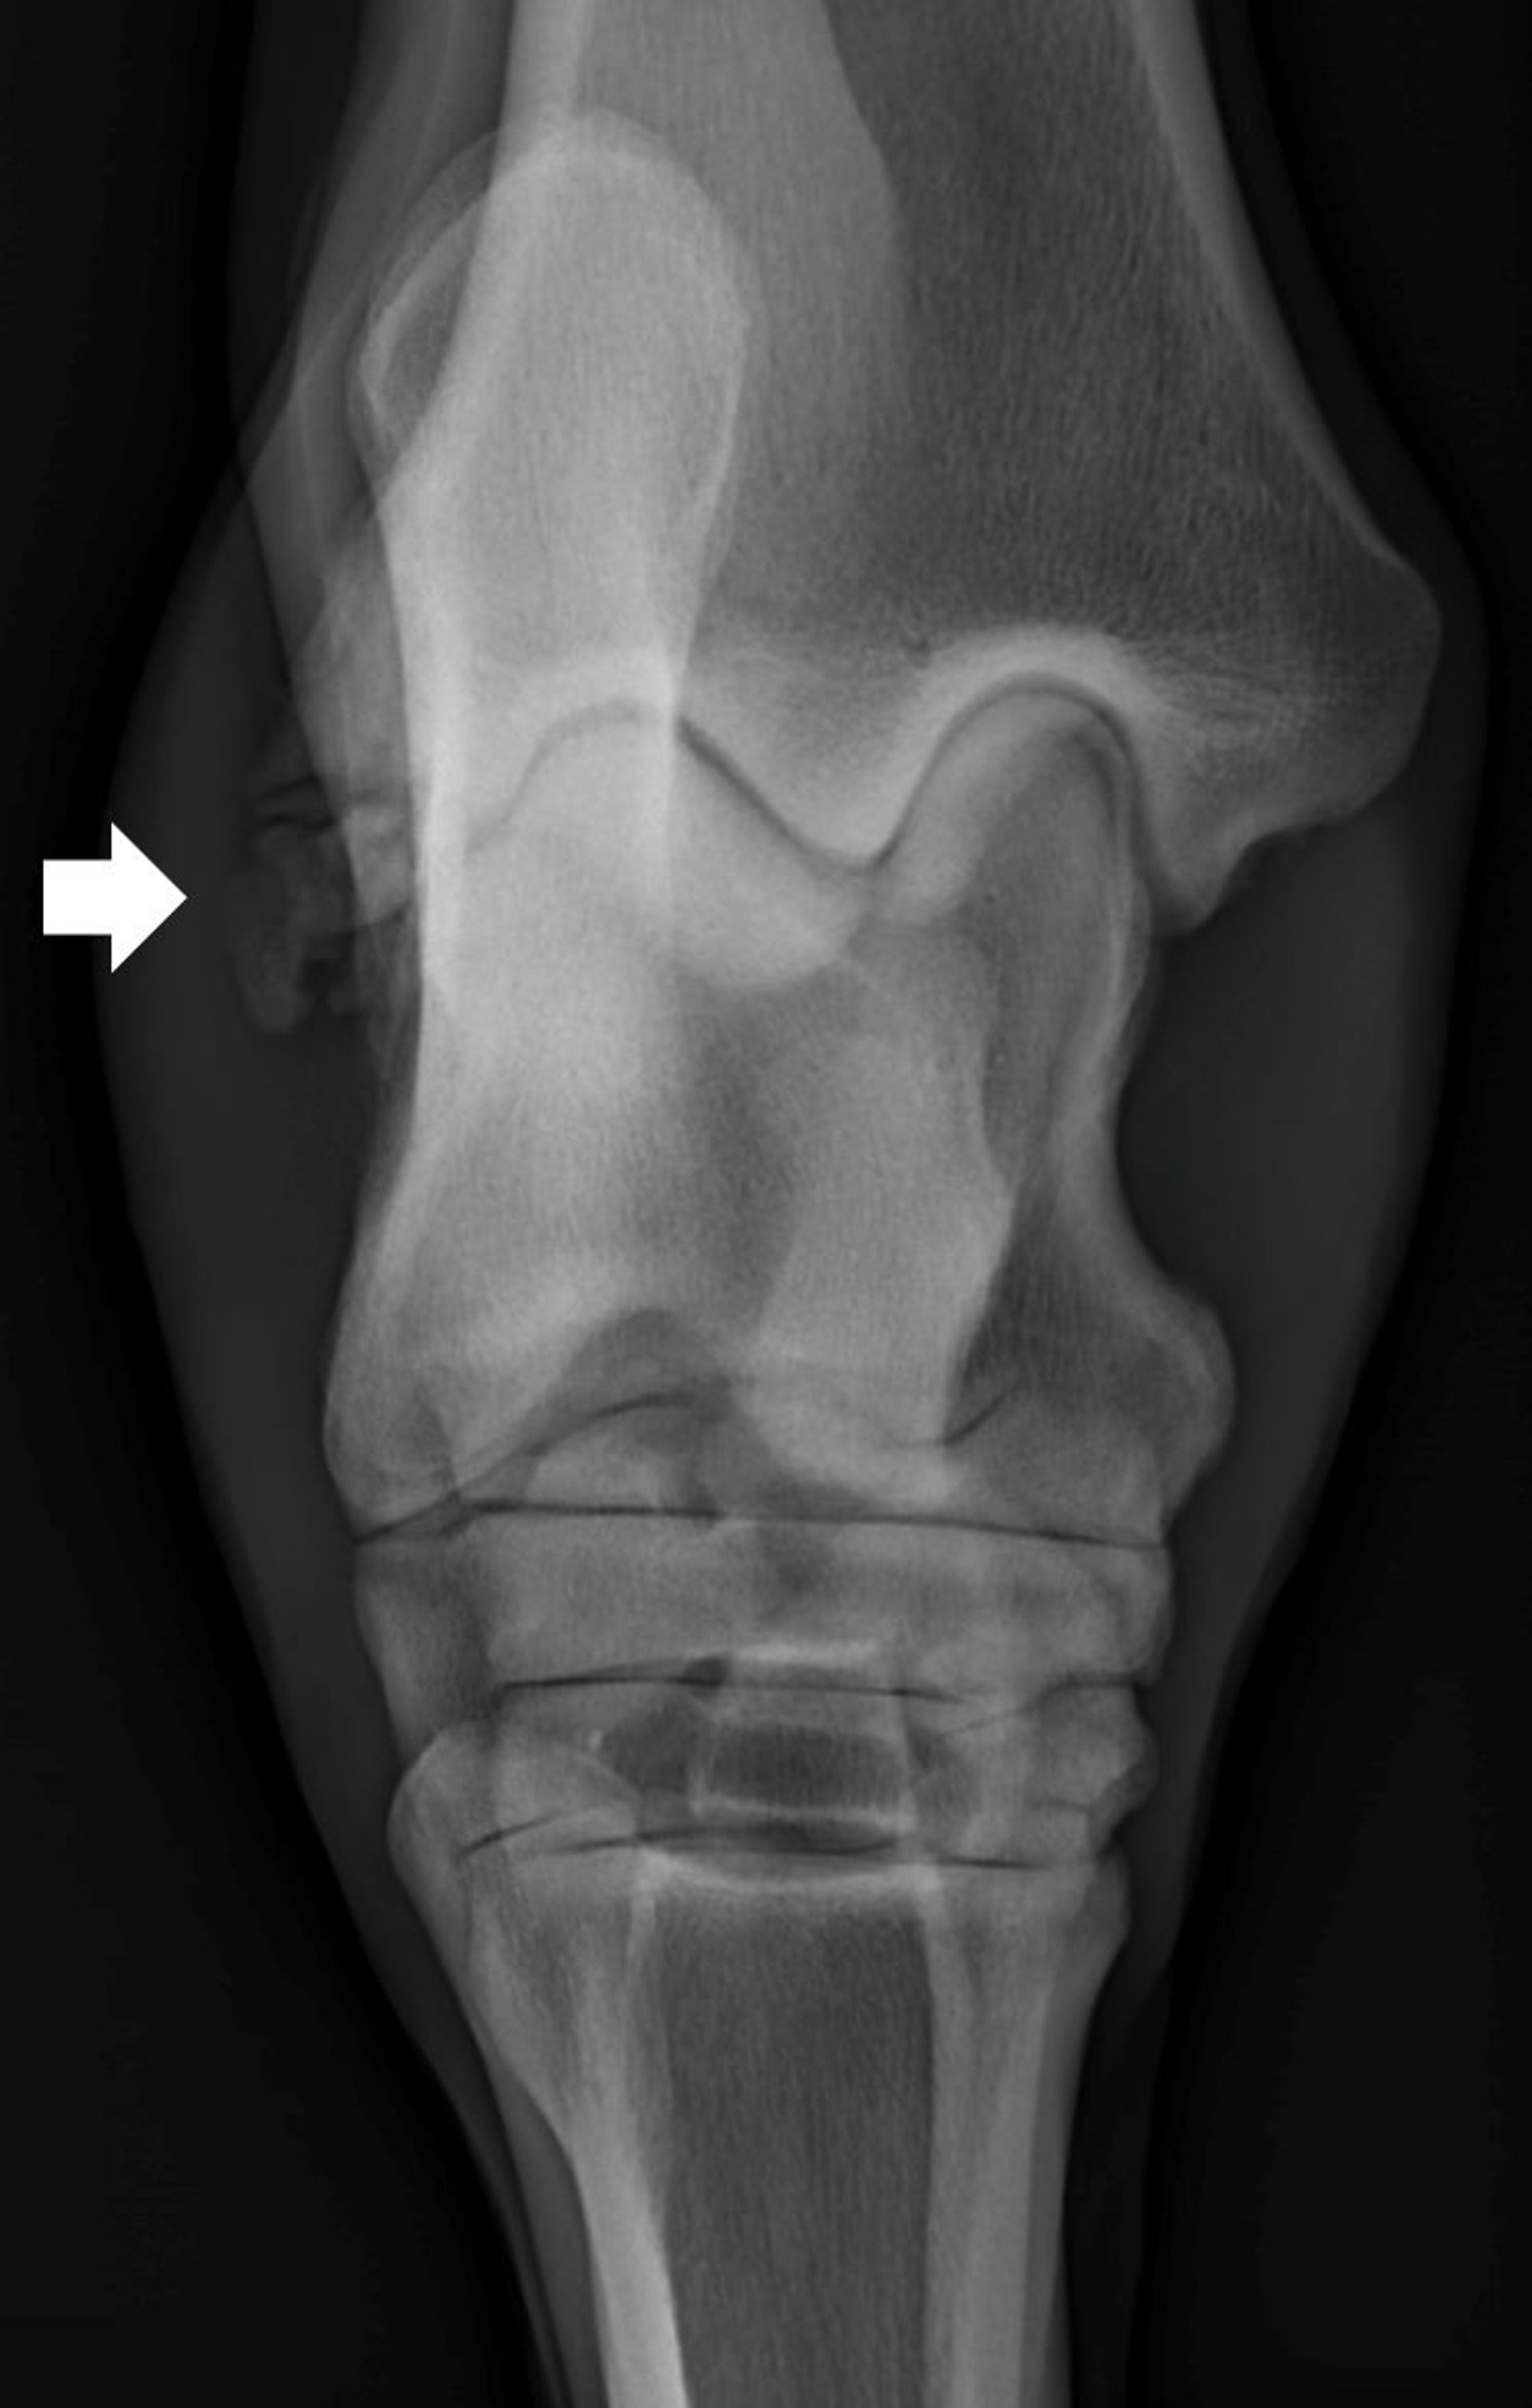

Dorsoplantar radiograph of a horse, demonstrating a chronic fracture (arrow) of the lateral malleolus of the tibia.

Courtesy of Dr. Hilary Rice.

Fractures of the lateral malleolus also occur (see ) and often involve damage to the short collateral ligament of the tarsus. These fragments are usually removed arthroscopically, which can be technically challenging because of the large number of soft tissue attachments on the lateral malleolus; arthrotomy is often required for complete removal of the fragment.